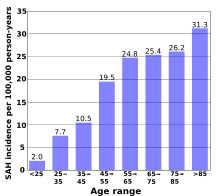

According to a review of 51 studies from 21 countries, the average incidence of subarachnoid hemorrhage is 9.1 per 100,000 annually. Studies from Japan and Finland show higher rates in those countries (22.7 and 19.7, respectively), for reasons that are not entirely understood. South and Central America, in contrast, have a rate of 4.2 per 100,000 on average.[63]

Although the group of people at risk for SAH is younger than the population usually affected by stroke,[4] the risk still increases with age. Young people are much less likely than middle-age people (risk ratio 0.1, or 10 percent) to have a subarachnoid hemorrhage.[63] The risk continues to rise with age and is 60 percent higher in the very elderly (over 85) than in those between 45 and 55.[63] Risk of SAH is about 25 percent higher in women over 55 compared to men the same age, probably reflecting the hormonal changes that result from the menopause, such as a decrease in estrogen levels.[63]